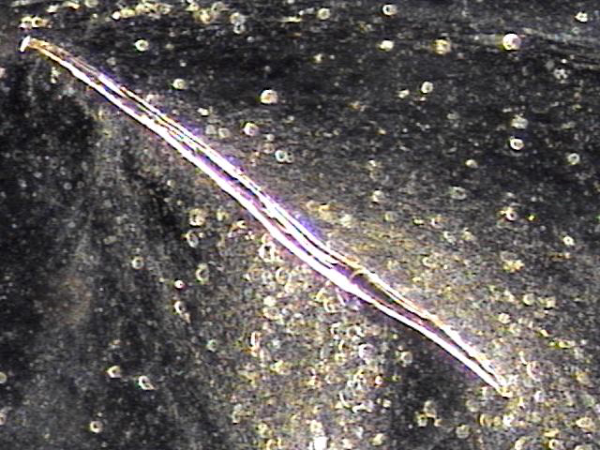

주 2회 전립선의 표적 치료후 전립선관과 사정관 입구와 사정관 내에 쌓여 있던 섬유소 덩어리의 치료된 자료 입니다.

This is post-treatment evidence showing the removal of fibrous clumps that had built up in the prostatic duct, at the entrance of the ejaculatory duct, and within the ejaculatory duct itself, following twice-weekly targeted prostate treatments.